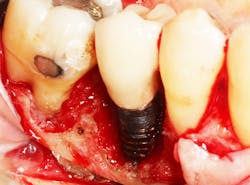

Recent studies suggest a role of SSRI intake and reduced bone mineral density, with an increase in bone fracture.4 The effect of SSRI use on implant success rates is not clear, but one study evaluated 94 implants placed over five years and saw a double in implant failure rates when comparing patients taking SSRIs and those not taking the medication.5 Another more recent study evaluated 2,055 implants placed over a two-year period. This study suggested a threefold increase in the number of failures in patients taking SSRIs compared to those who did not take the medication.6 When unexplained bone loss occurs around an implant and the patient has been on a long-standing SSRI medication, consideration should be given to this possible etiology (figure 1).

The effect PPIs have on implants is not clear, but one study looked at 3,560 implants placed in 1,000 patients over a 35-year period. Results found a 12% failure rate in PPI users versus nonusers.8 Another study evaluated 1,773 implants placed in 800 patients and found the failure rate doubled when comparing PPI users and nonusers.9 When unexplained bone loss occurs around an implant and the patient has been on long-standing PPI medication, consideration should be given to this possible etiology (figure 2).